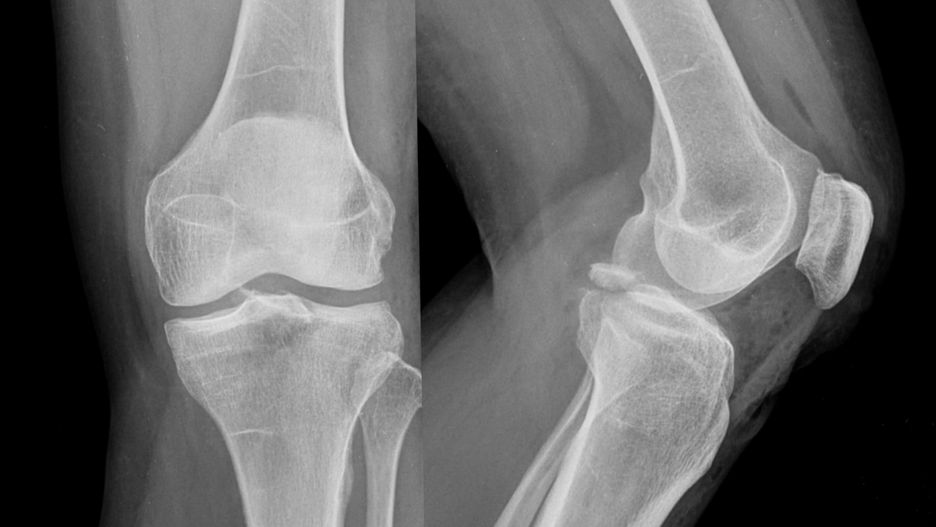

Złamanie awulsyjne najczęściej dotyczy okolic przynasadowychZłamanie awulsyjne najczęściej dotyczy okolic przynasadowych

Źródło zdjęć: © Adobe Stock

Złamanie awulsyjne występuje w miejscach umocowania ścięgien i więzadeł do kości. Najczęściej dotyczy okolic przynasadowych: kości skokowej, guza kulszowego czy kolca biodrowego.

• stawu kolanowego (rzepki),

Badania wykorzystywane w diagnostyce złamań awulsyjnych to RTG, rezonans magnetyczny (MRI), tomografia komputerowa (TK) i badanie ultrasonograficzne (USG). W przypadku urazu należy zasięgnąć porady ortopedy.